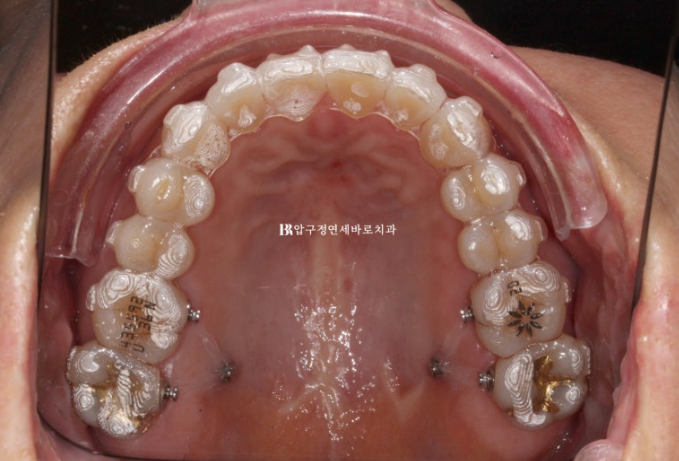

23.10

초기부터 입천장에 미니스크류를 심었습니다.

이때 예상되는 원치않는 치아이동을 피하기 위해 치아들의 각도와 토크, 위치를 조절하는 클린체크 치료계획이 또 매우 중요한 부분입니다.

클린체크 상의 치료결과를 예쁘게 만들면 절대로 실제 결과가 그렇게 나오지 않습니다.